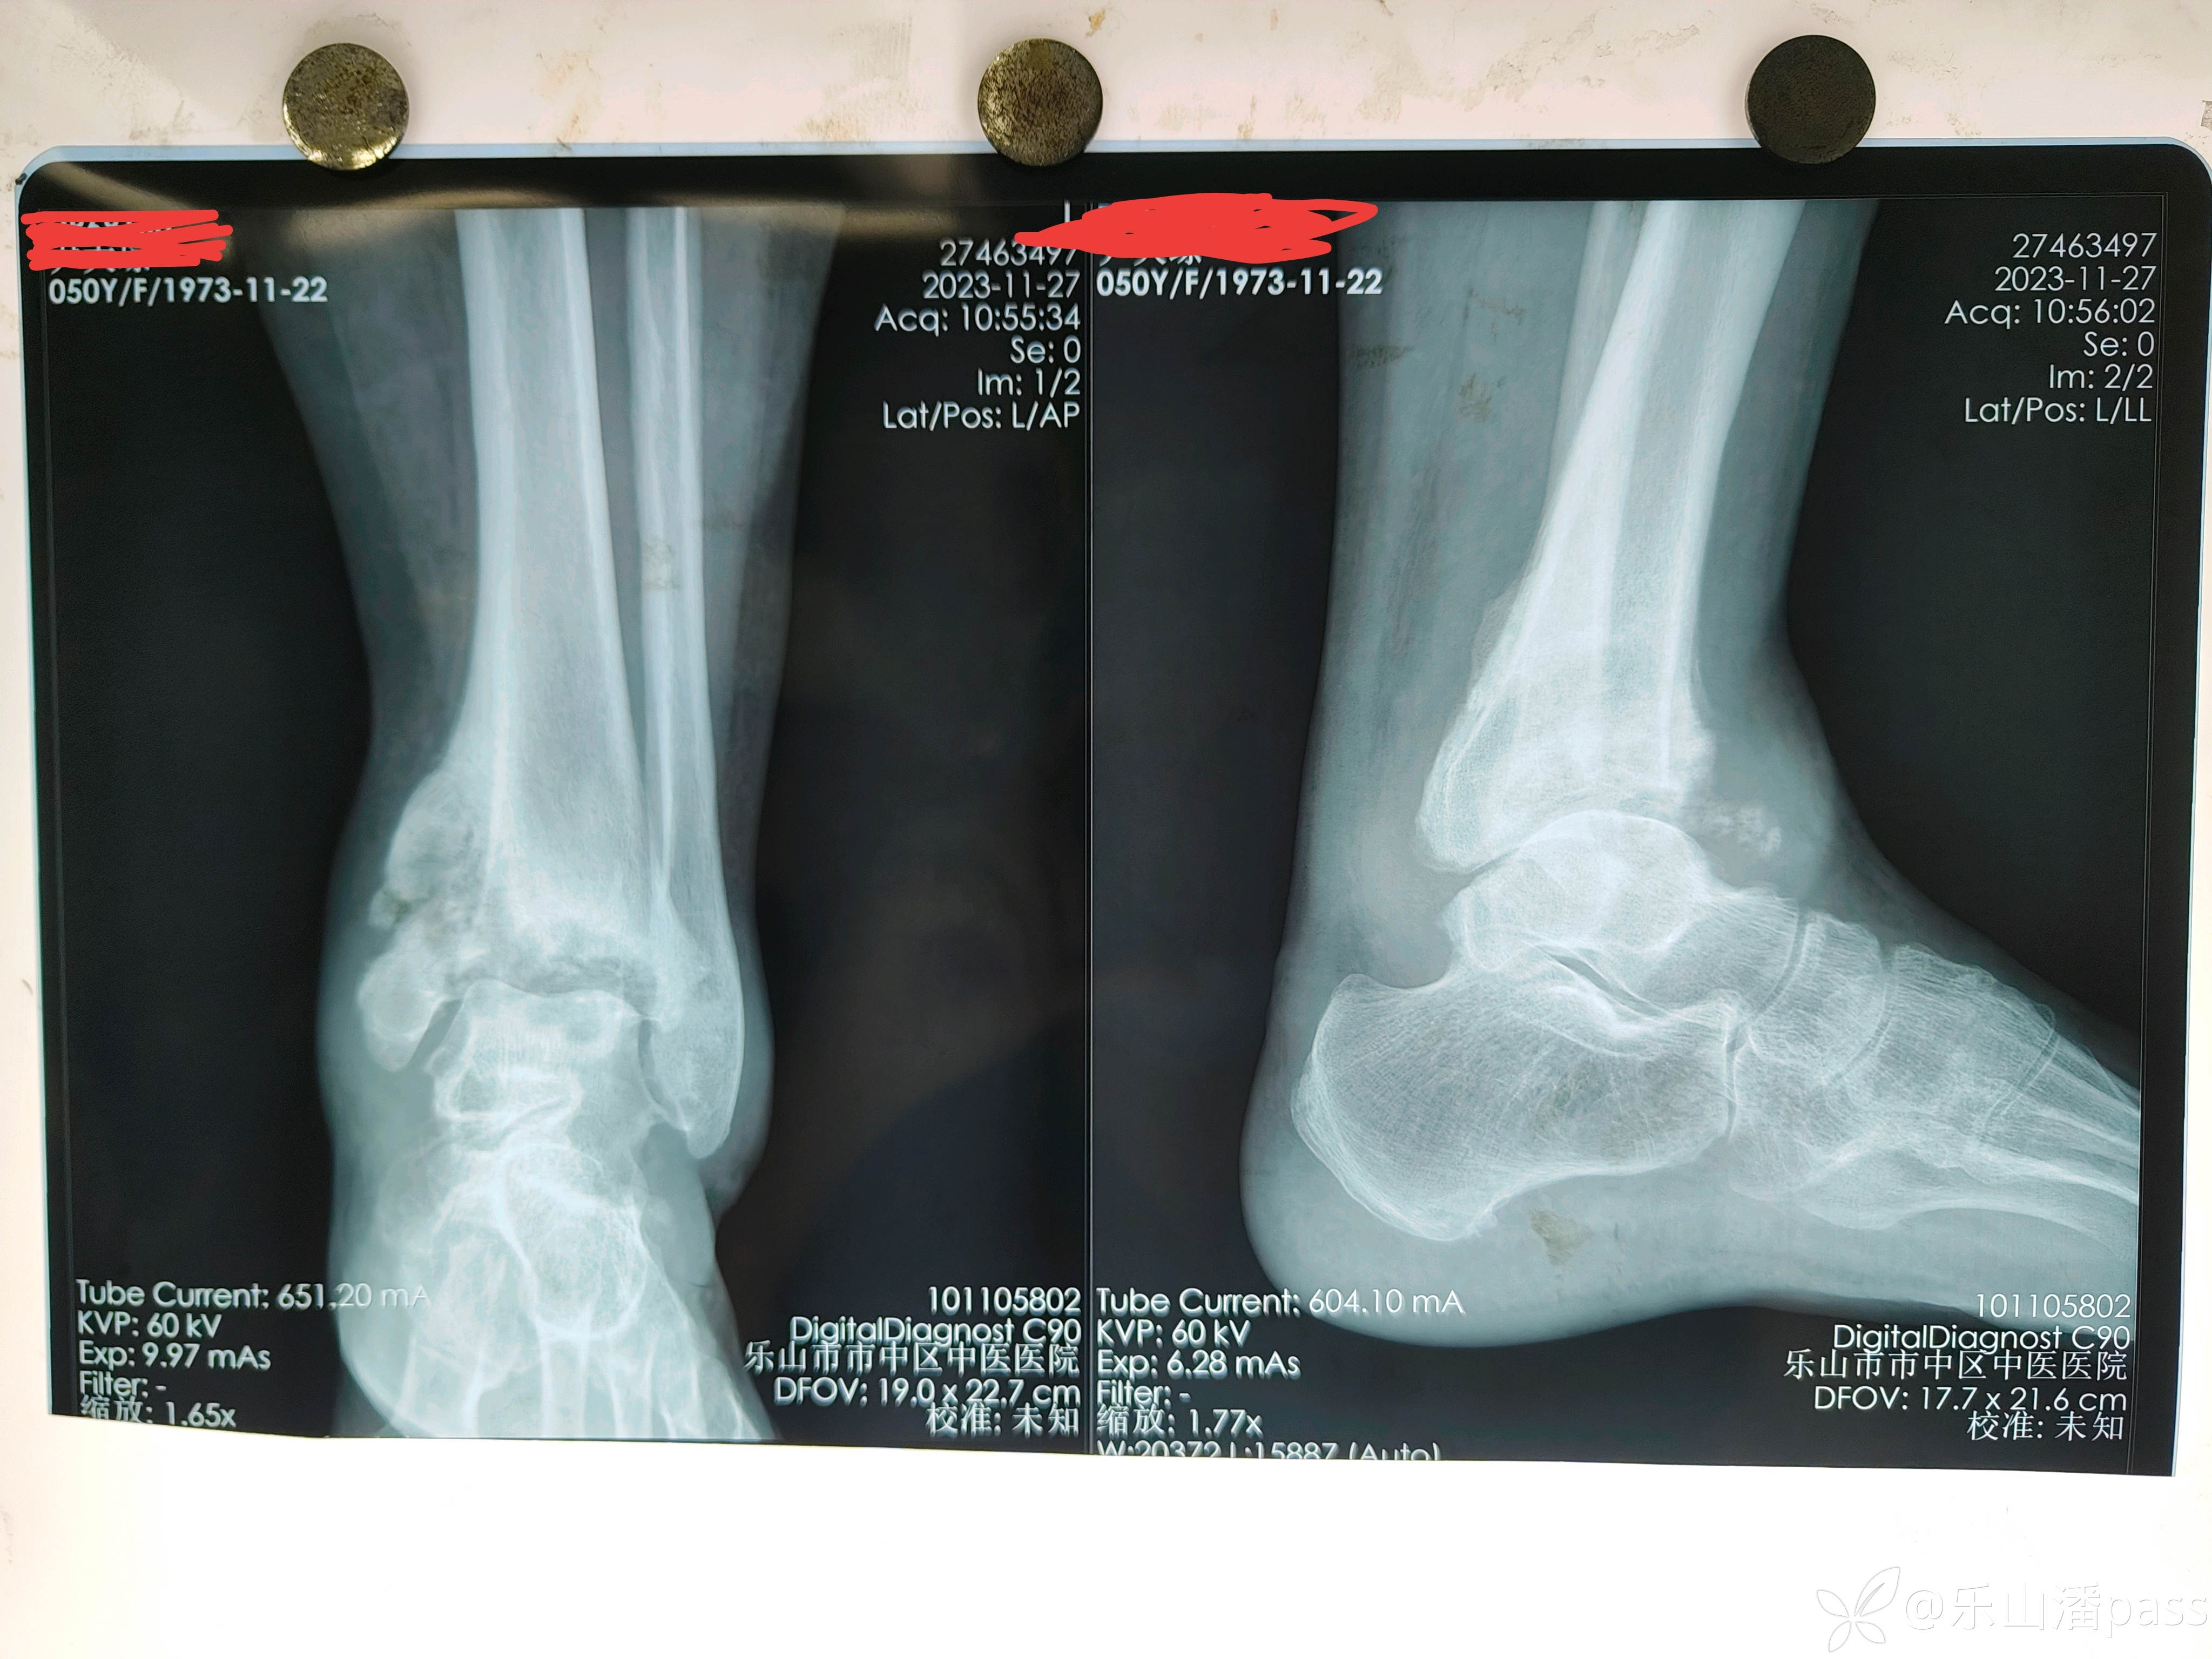

患者女性,自述十个月前外伤,患者就在当地医疗机构处理(具体处置不详)。原始片如下:

img